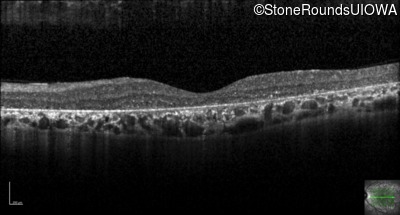

Optical Coherence Tomography - Right - 20/40 -1

Exemplar / OCT Stack

OCT Stack